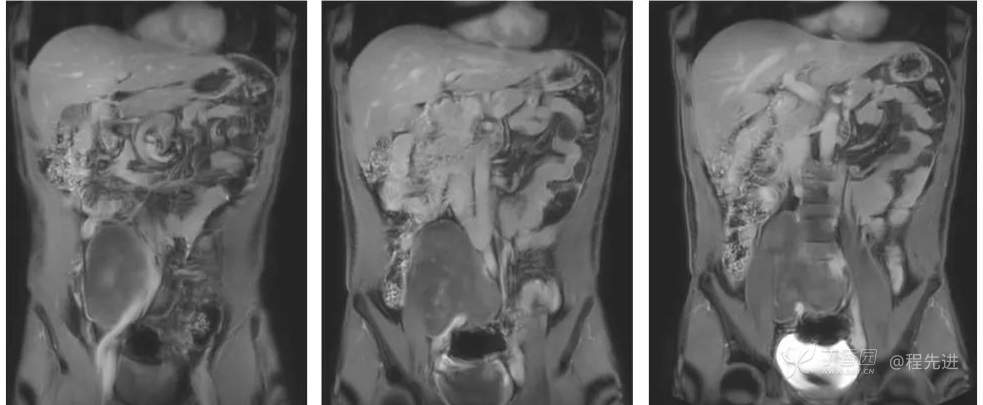

冠状位T2